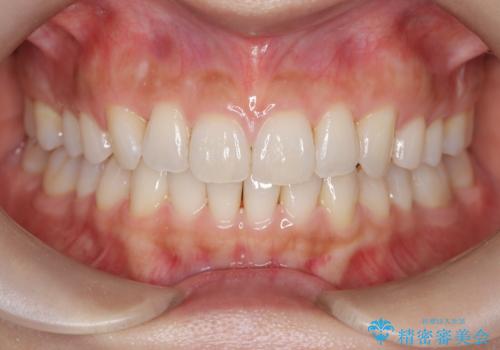

- 前歯の捻れと口元の突出を主訴に来院されました。

インビザラインを用いて上顎の遠心移動を行い、前歯を下げながら凸凹を綺麗に治すことができました。

歯を抜かない矯正治療を行う場合、口元は極端には変わりません。

今回は奥歯の遠心移動を行い、できる限り前歯を下げられるように治療を行いました。